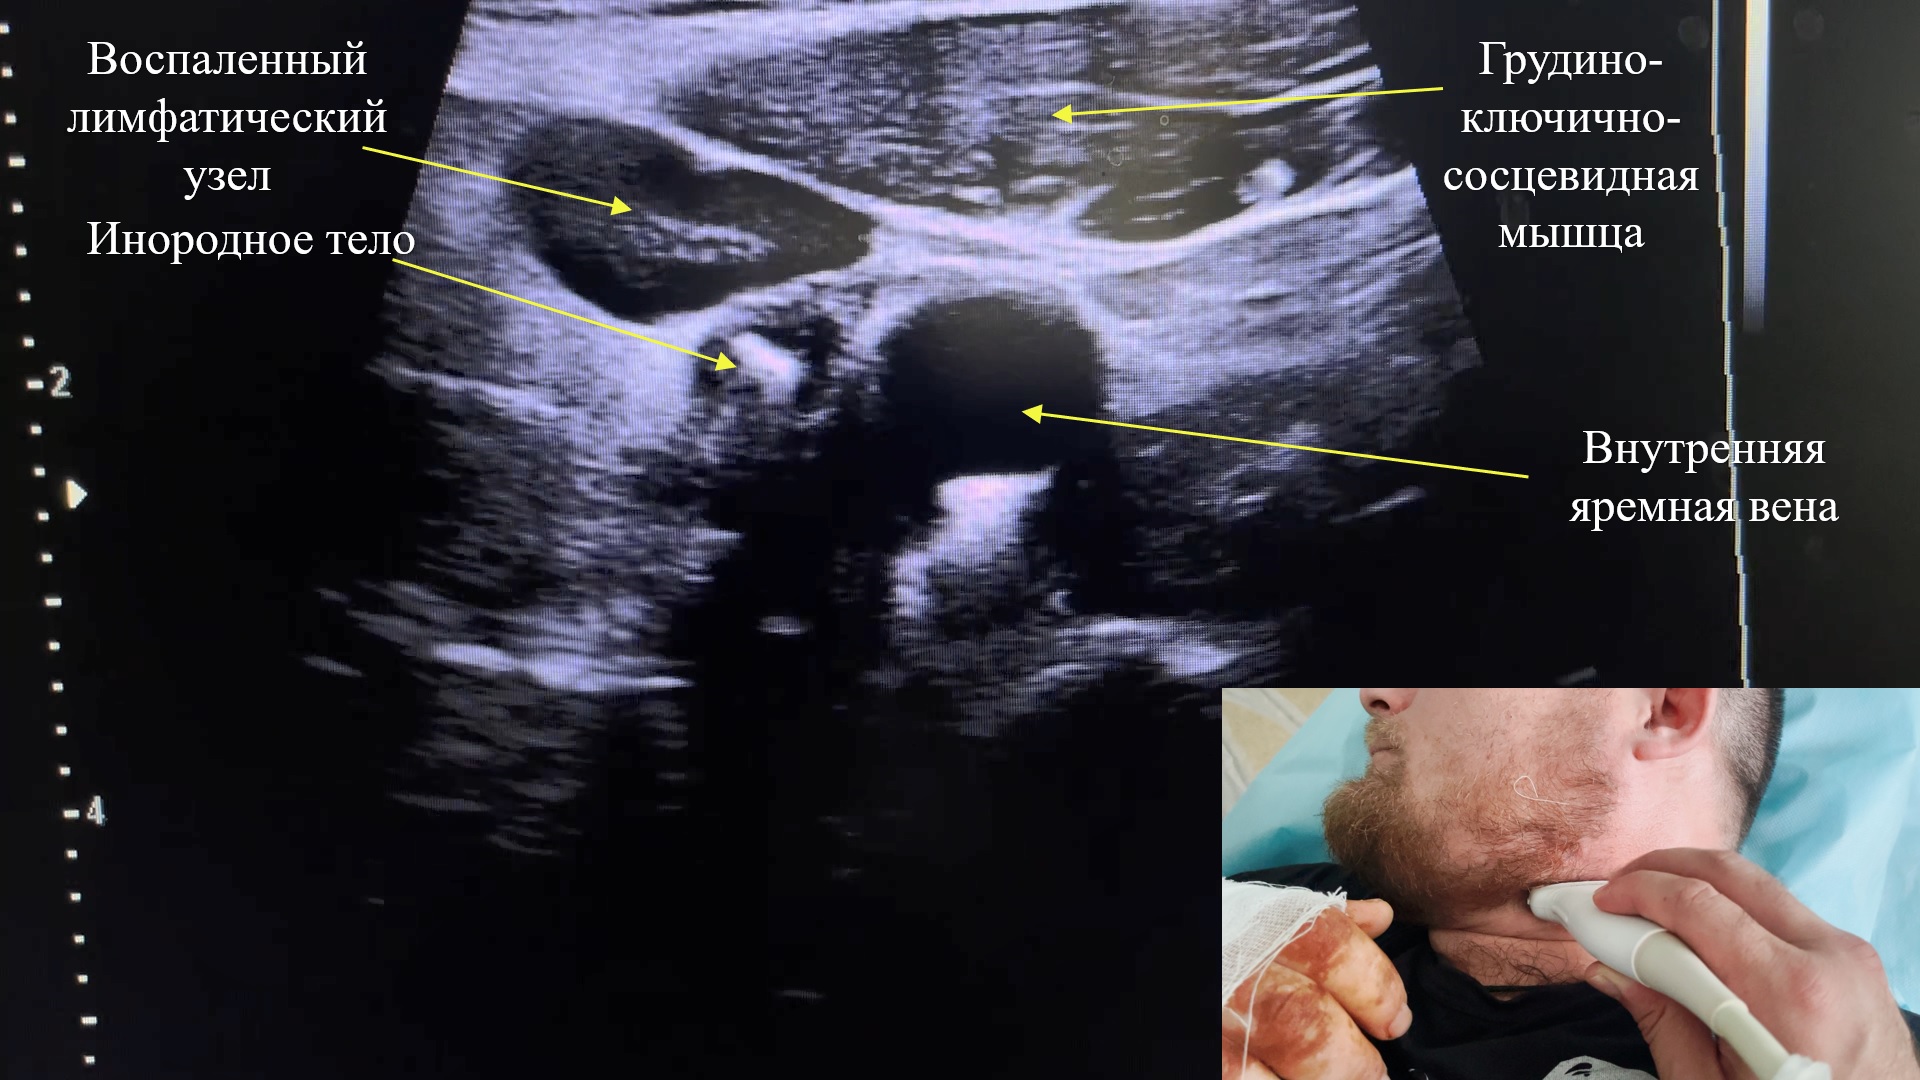

Во время ультразвукового исследования от 01.12.23 г. визуализировано инородное тело мягких тканей шеи до 8 мм в длину и 4 мм ширину (рис. 3), расположенное между внутренней яремной веной и областью бифуркации общей сонной артерии (рис. 4).

Рис. 4. Инородное тело, расположенное между внутренней яремной веной и бифуркацией общей сонной артерии.

Fig. 4. A foreign body located between the internal jugular vein and the bifurcation of the common carotid artery.